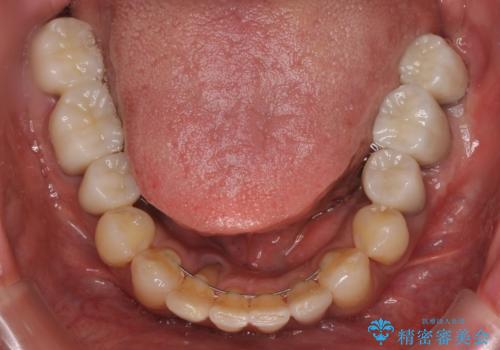

インプラント埋入後、手前のインプラント周りの丈夫な歯肉(角化歯肉)が失われてしまったため、角化歯肉の移植を行うこととなりました。

十分な角化歯肉が獲得でき、清掃性の高い環境が達成されました。